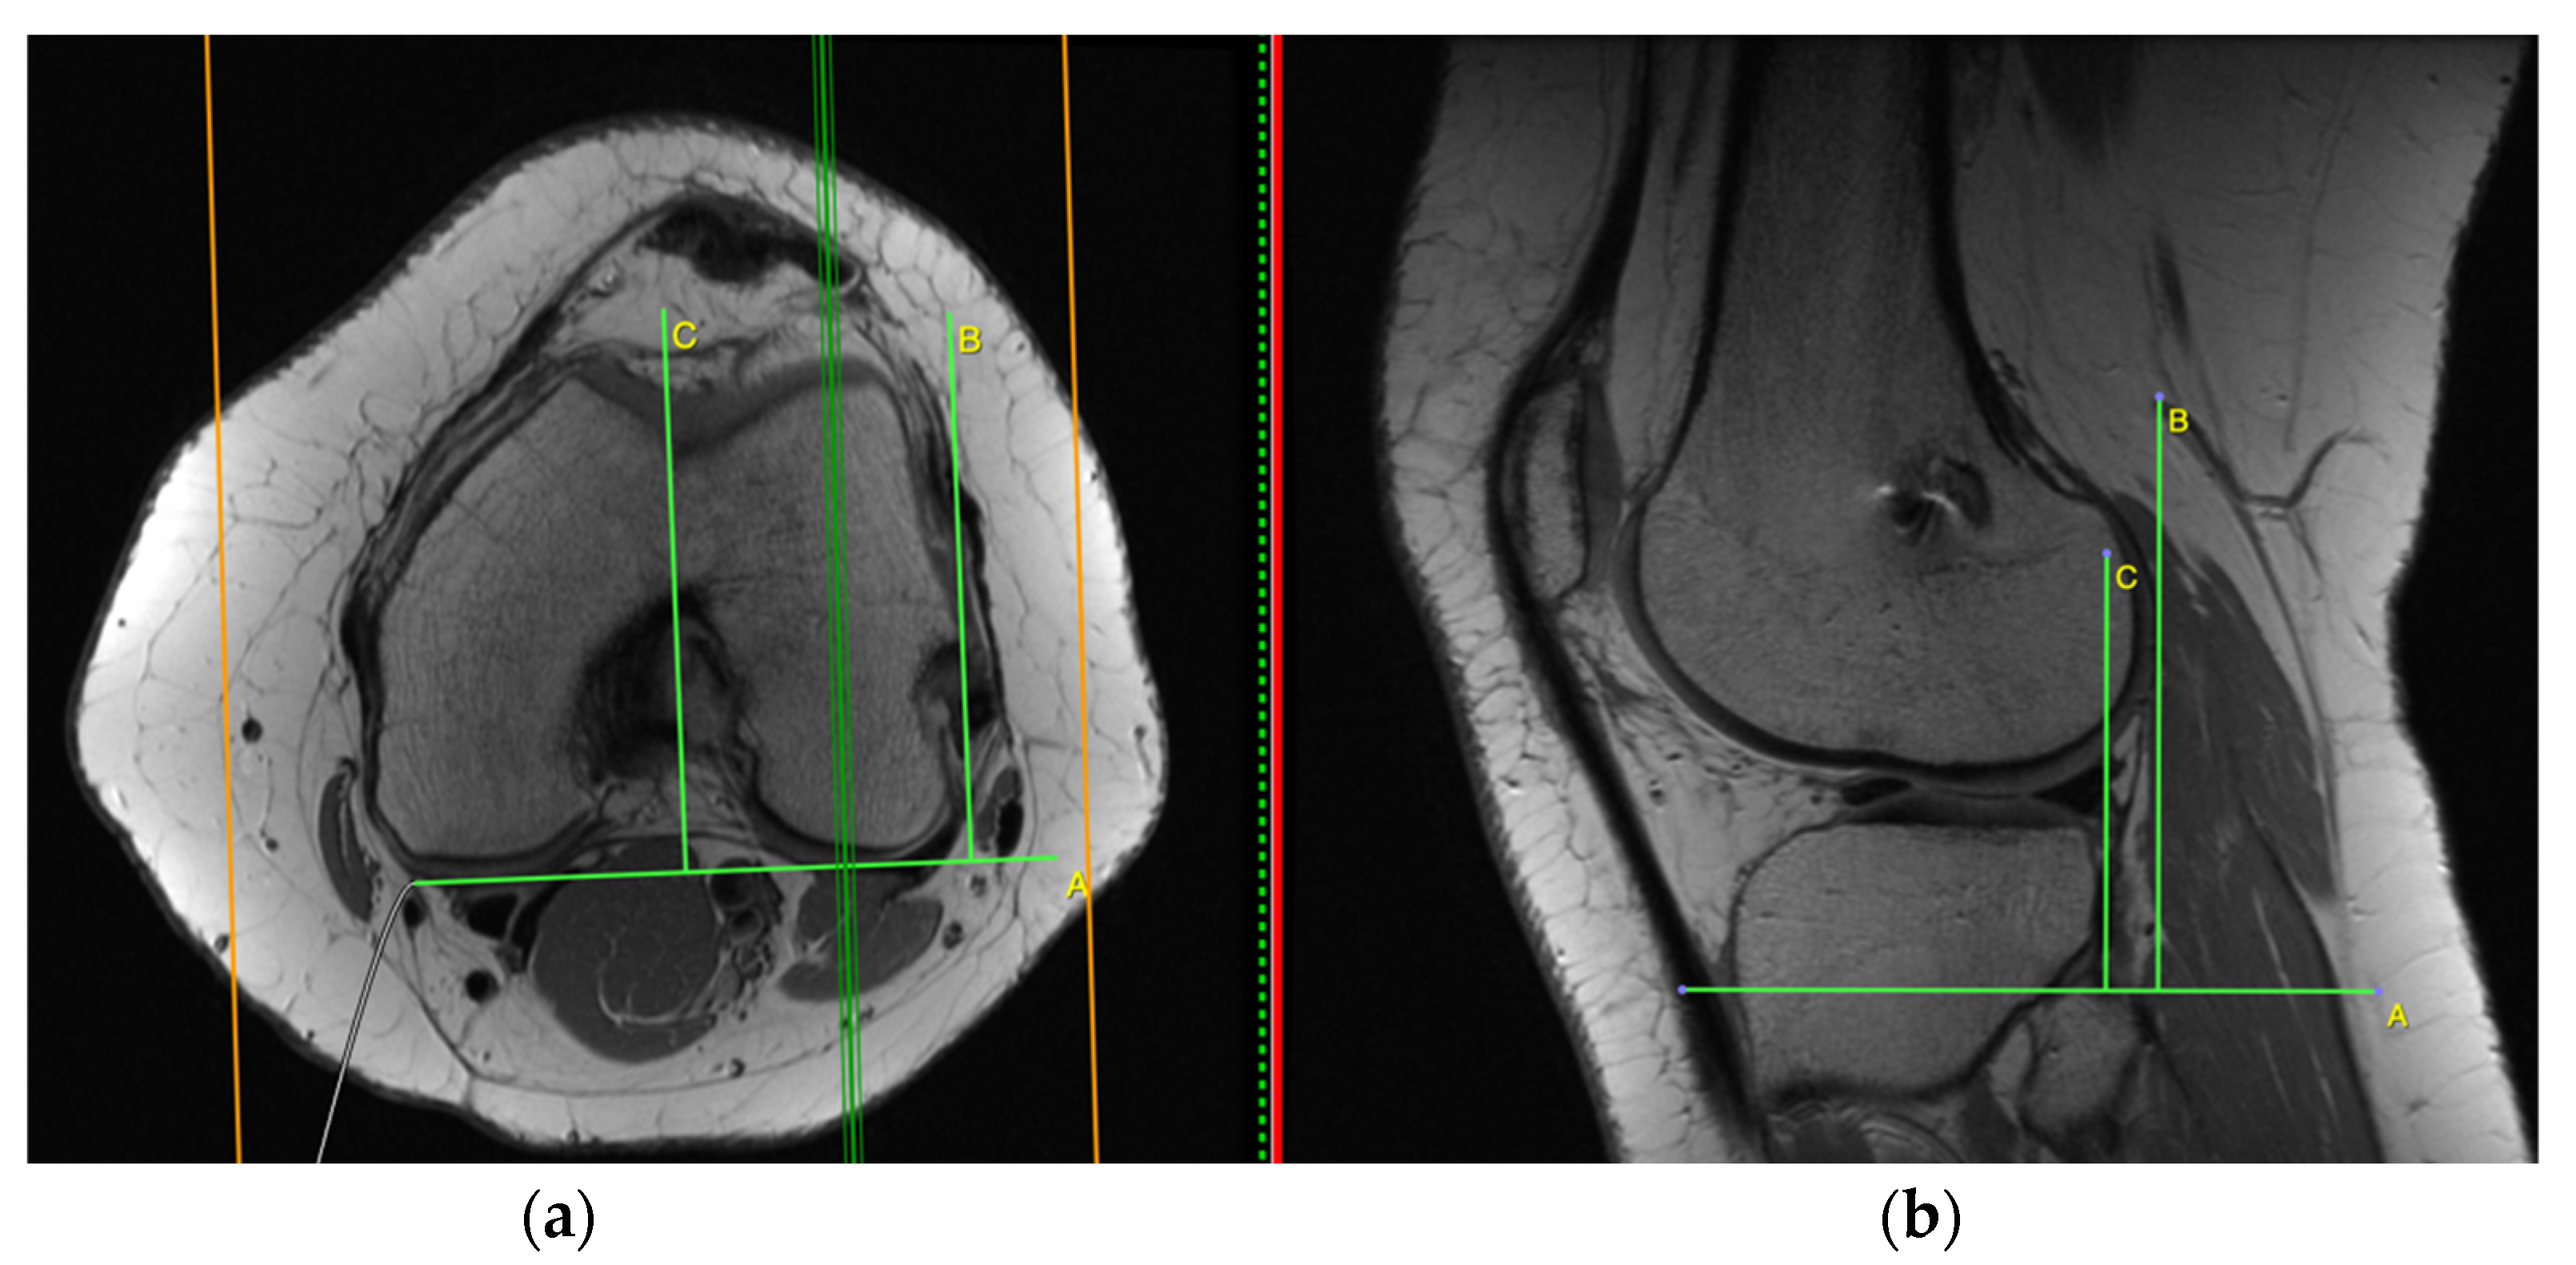

2.1. Measurement on the Sagittal Plane

2.2. Measurement on the Axial Plane